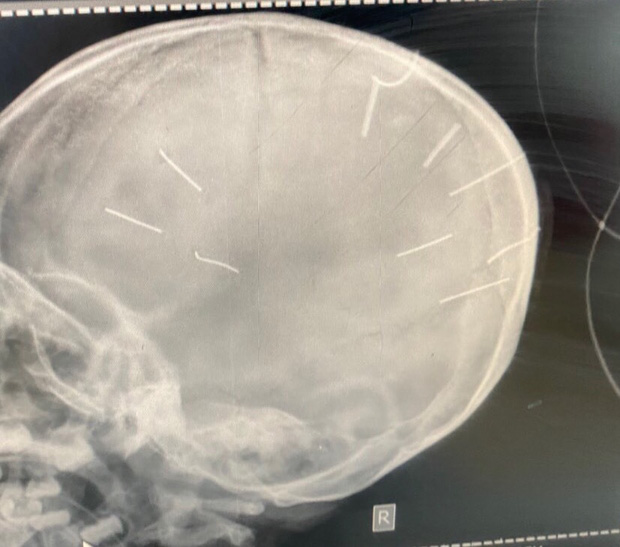

Hình ảnh chụp X-Quang hộp sọ bệnh nhân với 9 hình thể nghi là đinh (Ảnh: Bệnh viện Đa khoa huyện Thạch Thất cung cấp)

Bệnh viện Đa khoa Xanh Pôn đã tiến hành chụp cắt lớp dựng hình, nhận thấy có những hình ảnh giống như đinh gỗ ở sọ và tổ chức não, tổng cộng 9 cái.